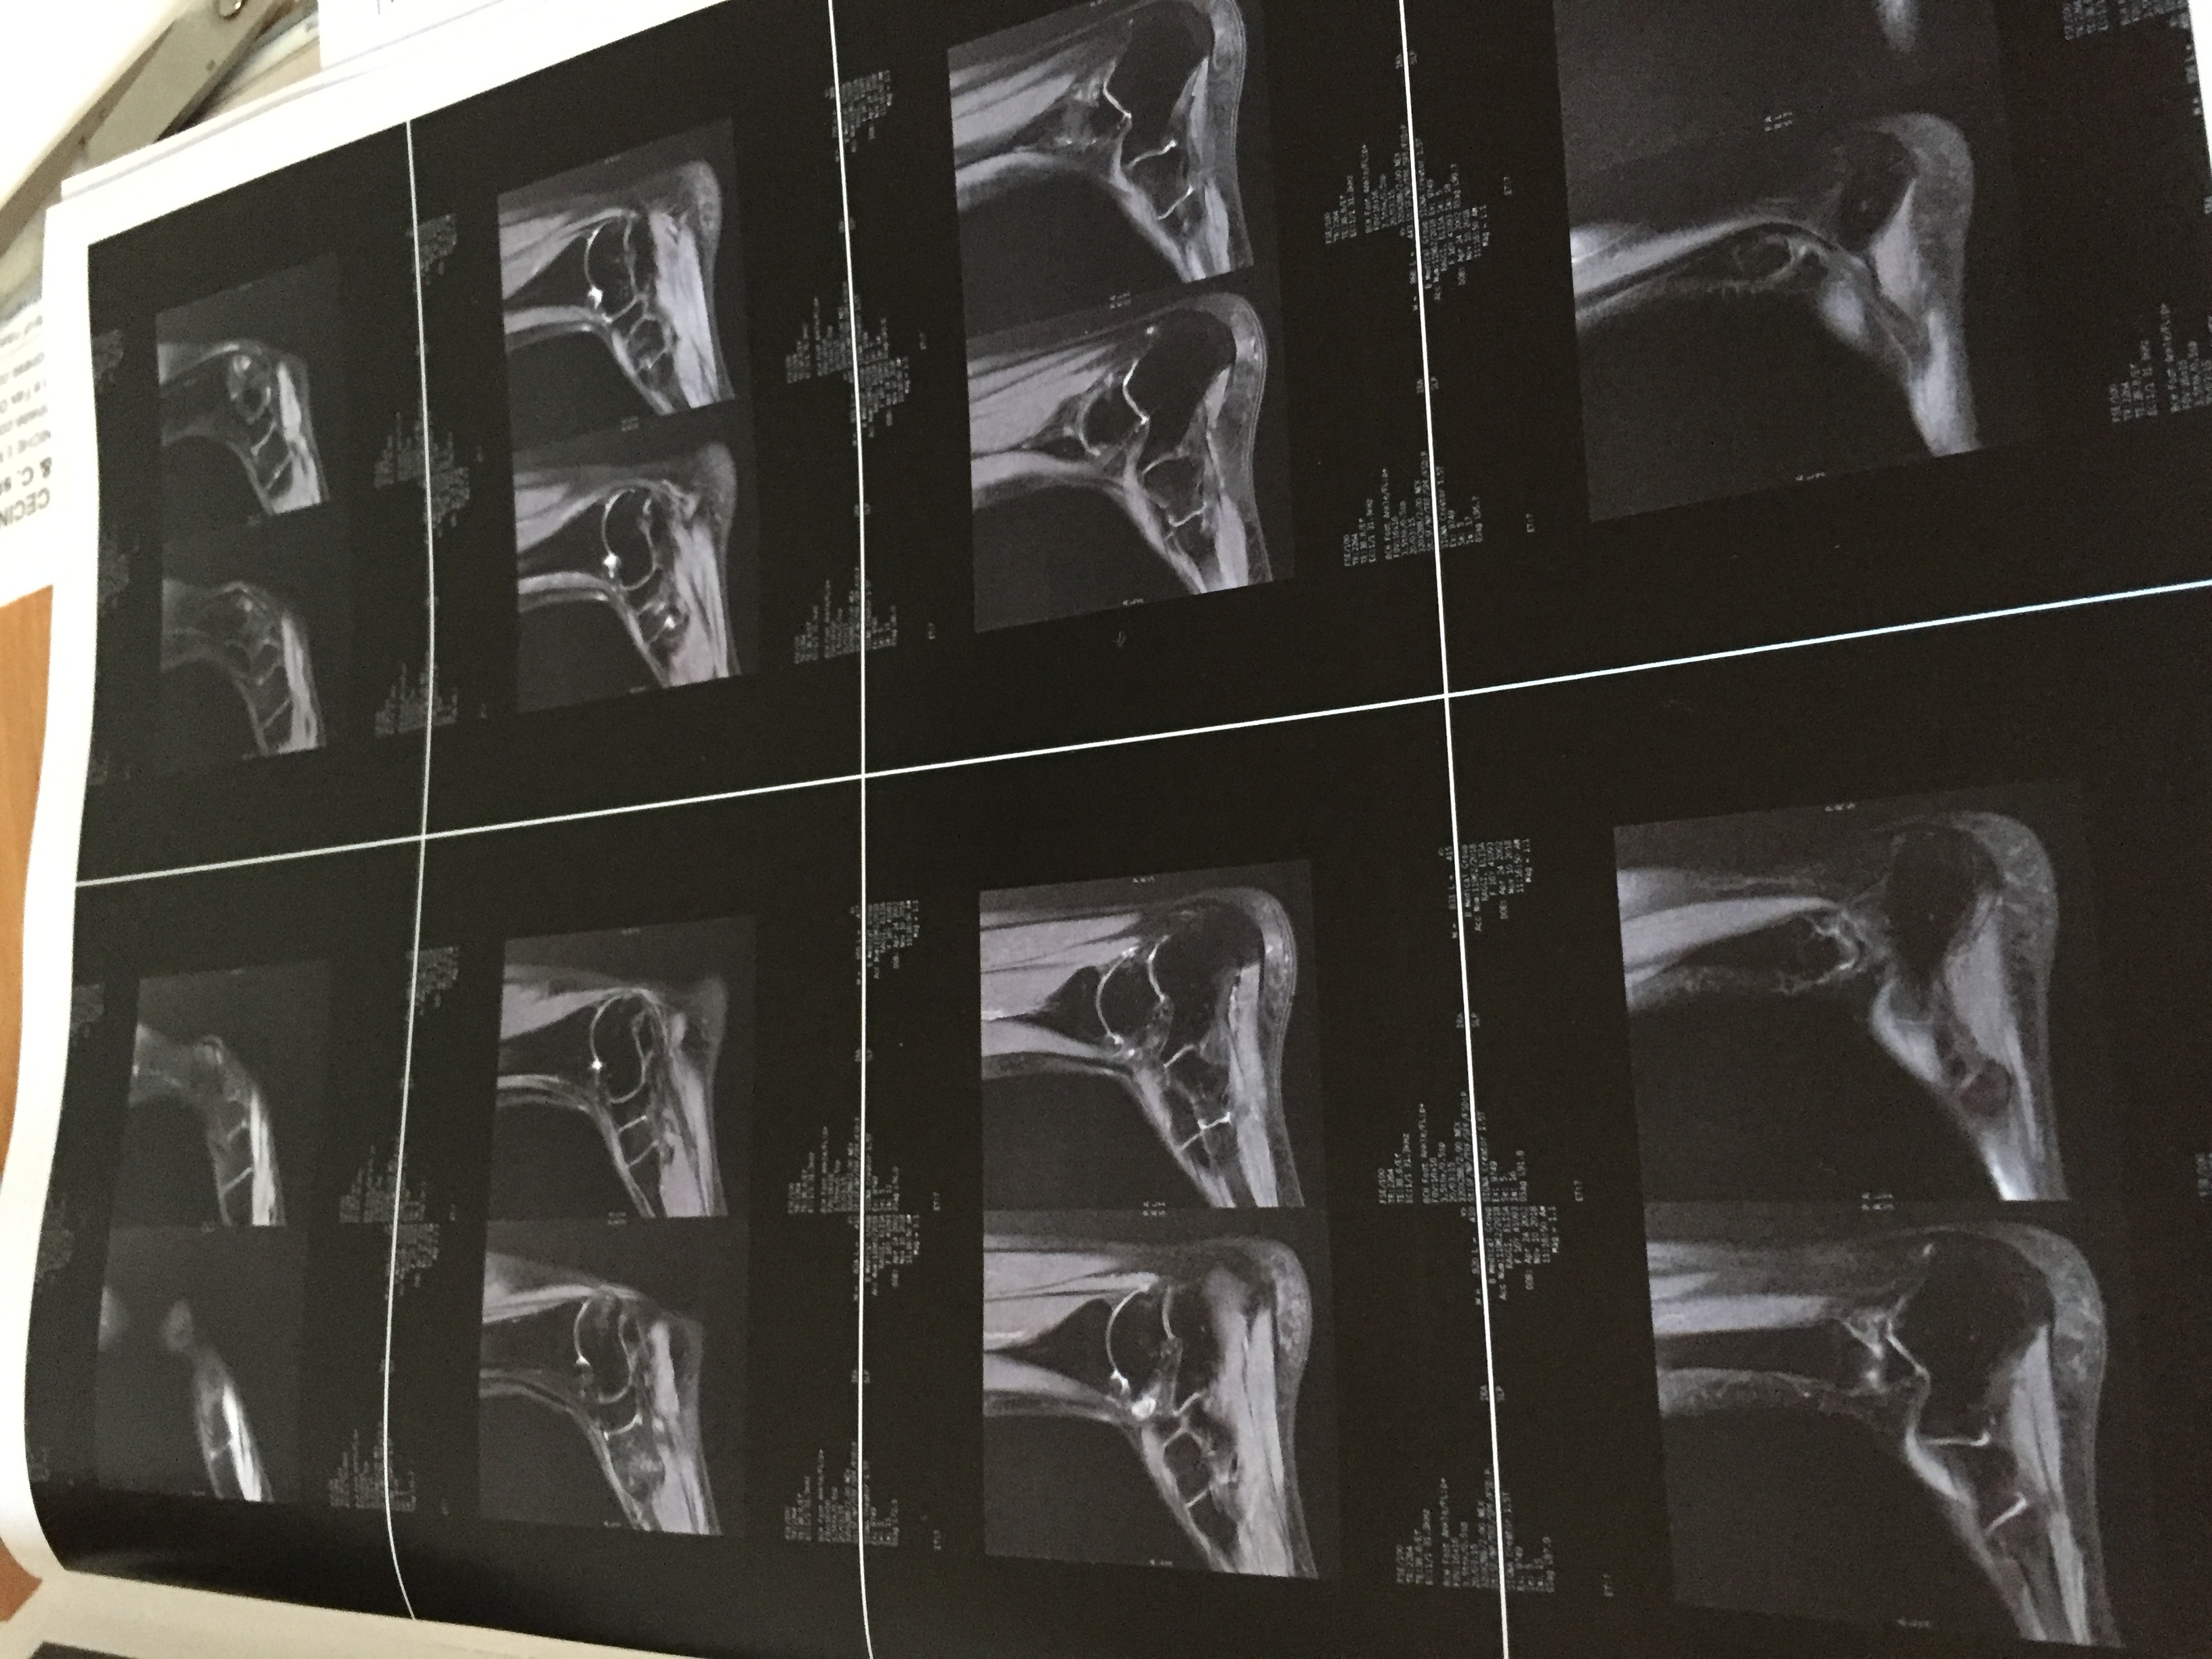

Buongiorno mia figlia ginnasta è circa 1 mese che dolore all collo del piede dopo 17 laserhag poco miglioramento

Le invio delle foto della rm , può darmi informazioni?

7725915C-94CD-4F13-B547-D9E91C258238.jpeg

[ 1.36 MiB | Osservato 750 volte ]